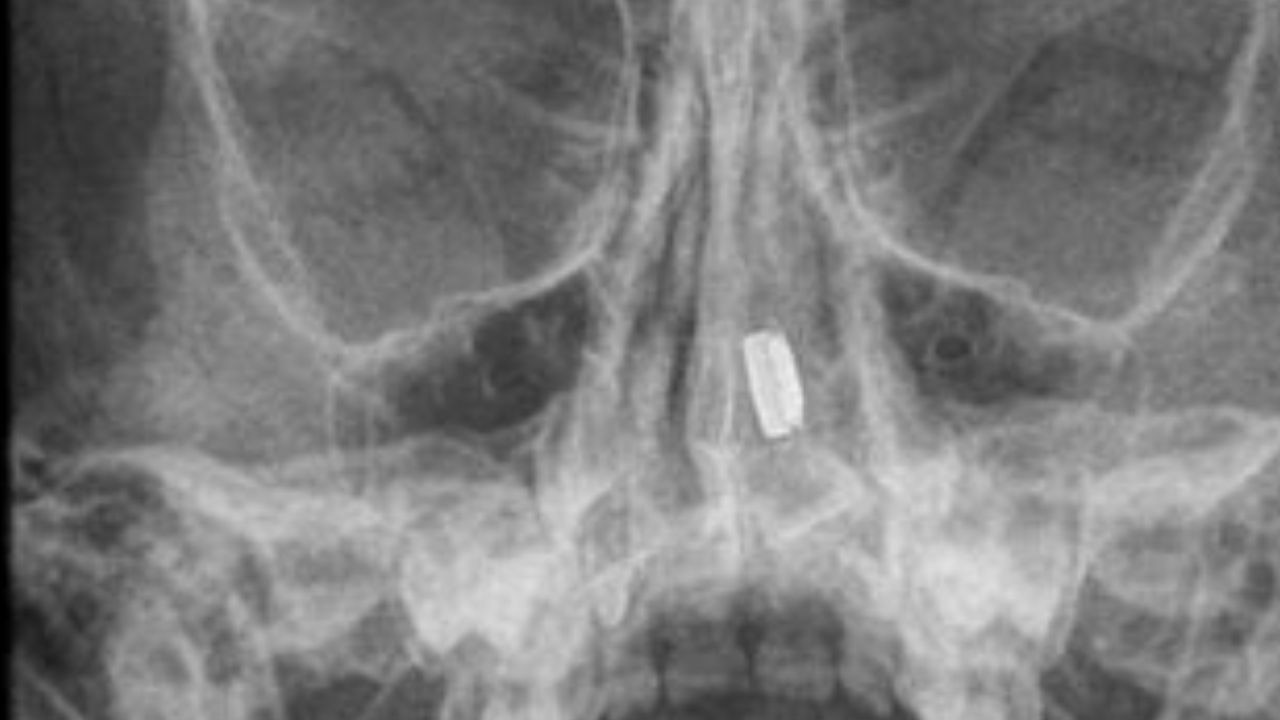

X-rays: Used in some cases to locate metallic objects like button batteries.

Tip: Avoid attempting removal at home unless you’re certain it’s safe.